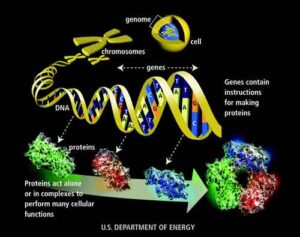

Scienziati finlandesi, tedeschi e canadesi hanno identificato anormalità genetiche associate alla riprogrammazione di cellule adulte in cellule staminali pluripotenti indotte...